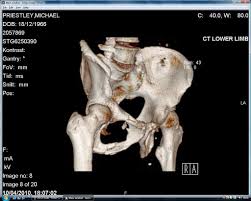

걷거나 앉았다 일어날 때, 혹은 한쪽 다리가 유독 불편하게 느껴질 때 고관절 문제를 의심해보는 분들이 늘고 있습니다. 고관절은 몸의 중심을 지탱하는 중요한 관절로, 문제가 생기면 일상생활 전반에 불편함이 나타나는 경우가 많습니다. 특히 초기에는 단순한 근육통이나 허리 통증으로 오해하기 쉬워 치료 시기를 놓치는 경우도 적지 않습니다. 이번 글에서는 고관절 통증이 있을 때 나타나는 대표적인 증상을 상황별로 알기 쉽게 정리해보겠습니다.

고관절 통증이 나타나는 위치

고관절 통증은 엉덩이 깊숙한 부위에서만 느껴진다고 생각하기 쉽지만, 실제로는 다양한 위치로 퍼져 나타날 수 있습니다.